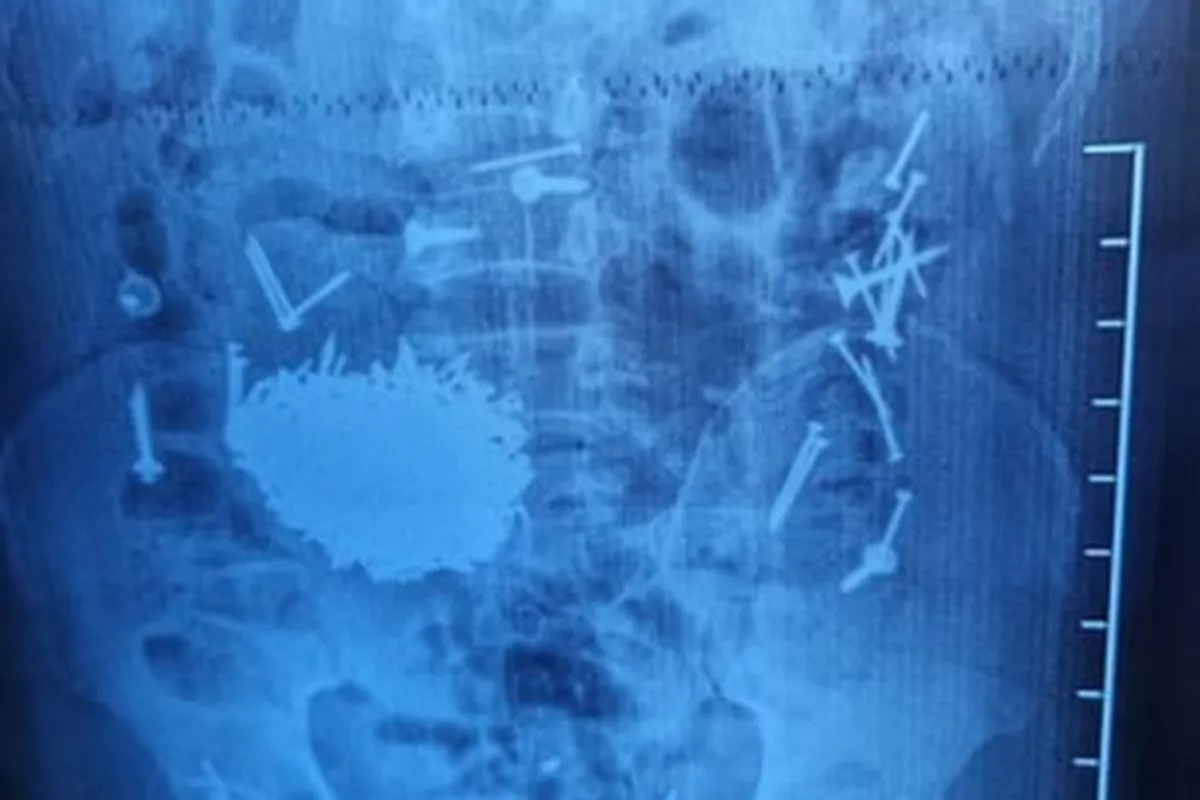

Diagnostic tests revealed a shocking cause: the patient’s gastrointestinal tract contained a large number of metallic objects, including nails and screws, The Caspian Post reports via Uzbek media.

Doctors decided to perform an emergency surgery, using laparotomy and gastrostomy techniques. Around 200 grams of metal objects were successfully removed from his abdomen. Senior physician Yuldosh Kuliyev said that the procedure took about one hour.